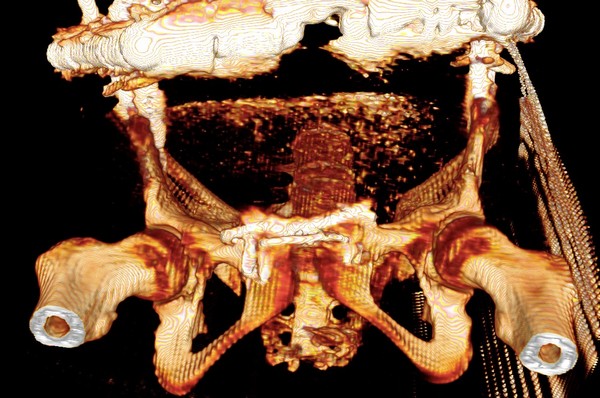

Девочка 14 лет. Кататравма (падение с высоты 4-5 этажа). Вертикально нестабильный перелом таза со смещением, разрывом лонного и левого подвздошно-крестцового сочленения, перелом крестца, открытый перелом костей голени. Ребёнок оперирован на 10-е сутки после травмы - выполнили максимально возможную репозицию на ортопедическом столе, синтез лонного сочленения реконструктивной пластиной (из имеющихся пластин - на 7 дыр - самая длинная, получилось только по 2 шурупа с каждой стороны, поэтому пришлось подстраховаться проволокой), АВФ. Задний комплекс не фиксировали ввиду отсутствия канюлированных (да и неканюлированных)шурупов должной длинны.В настоящий момент перед нами стоит вопросов:1. Обязательно ли фиксировать подвздошно-крестцовое сочленение, либо фиксации АВФ будет достаточно? Аппарат стоит достаточно стабильно, девочка при перемещениях в пределах постельного режима болевых ощущений не испытывает.2. Что делать с отломком крестца, который довольно значительно смещён кпереди? В настоящий момент никаких проблем с дефекацией у больной нет, хотя, глядя на КТ, создаётся впечатление, что отломок прямо-таки лежит на прямой кишке. Репонировать-фиксировать? Просто удалить? Вообще не трогать? Не создаст ли он в дальнейшем проблем во время родов?Хотелось бы знать мнение уважаемых коллег.Заранее спасибо.

Здравствуйте, Сергей! Нестабильный перелом типа С подлежит обязательной задней фиксации или илиосакральными винтами, или пластиной, или стяжкой (кто что лучше умеет и чем оснащен). Возможен циркулярный АВФ (Уральский НИИТО). В Вашем случае, при невозможности восстановления заднего комплекса,- постельный режим до 2-х месяцев. Учитывая недостаточную репозицию в крестцово-подвздошном сочленении в будущем девочка обречена на хронический болевой синдром. Может быть стоило выполнить репозицию отломков в аппарате, а вторым этапом делать погружной остеосинтез. Костный фрагмент, думаю, можно оставить. После такой травмы речь будет идти о кесаревом сечении, а не о родах естественным путем.

Это не частый случай в детской практике. Вы очень хорошо сопоставили и фиксировали переднее полукольцо. Крестцово-подвздошное осталось в приличном смещении. Прекрасно - что нет неврологической клиники. Сейчас больная лежит. Поэтому всё хорошо. Учитывая соотношение крестец-подвздошная кость - кажется, что первые же проблемы возникнут при попытке поставить больного на ноги. Разорваны важнейшие стабилизирующие и воспринимающие нагрузку связки в системе позвоночник-крестец-таз. В таком положении фрагменов их адекватное восстановление и последующее функционирование , как мне кажется, не возможно. В возрасте 14 лет это взаимоотношение критично. Я имею в виду отсутствие репозиции. появление нестабильности, по-видимому, будет неизбежно. Это моё маленькое скромное мнение. Всё же надо было начинать сзади. Именно с репозиции. Фиксацию, ИМХО, можно было бы на безрыбье временно сделать и спицами (например-с резьбой) интраоперационно. В идеале - с навигатором, чтобы не задеть крестцовый канал, или с пальцем, контролирующим положение отломков над гребнем подвздоной кости и "навигирующим" проведение спицы. Сейчас Вам это сделать помешает LCP, жёстко фиксирующая переднее полукольцо и смещенное положение отломков. АВФ не "прижмёт" подвздошную кость к крестцу, и не выполнит репозицию. Возраст больной, мне кажется, не простит в дальнейшем погрешность в положении костей и, чем дальше, тем труднее будет исправлять . Это только мнение и ничего личного.Прямая кишка здесь в меньшей степени заинтересована - это вовсем не главное. Вероятные роды в насоящей тактике лечения совсем не играют решающей роли. Всё же - как неврология?